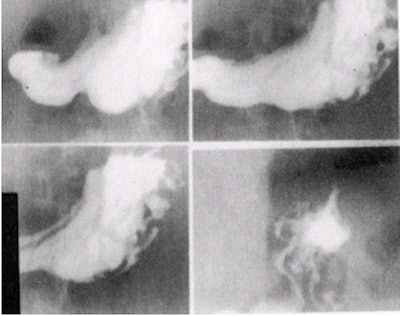

![]() |

| Images of the duodenal bulb in four slightly different views (10 x 12 image receptor, 4 on 1). Image courtesy of Dr. Naveed Ahmad. |

- With the tabletop horizontal and patient in right lateral position, image the duodenal bulb. Visualize the barium-filled duodenal bulb and obtain at least four slightly different views. If the bulb is not well seen, have the patient inhale deeply and stop breathing briefly to improve visualization of the bulb. Alternatively, the patient can be placed prone and the duodenal bulb can be compressed from underneath by using a balloon compression paddle.